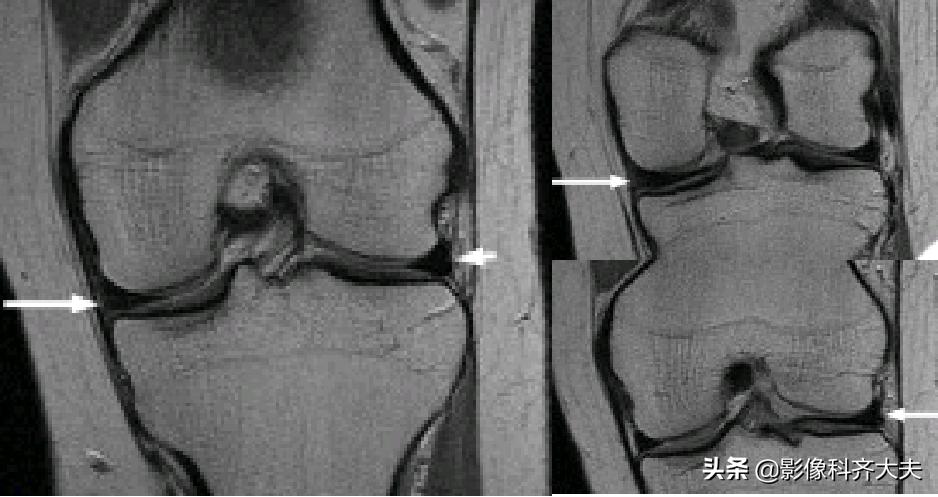

容易误诊为半月板损伤的正常解剖结构

膝横韧带:

腘肌腱腱鞘:

后股板韧带:

关节内气体伪影:

内侧半月板后角上隐窝: